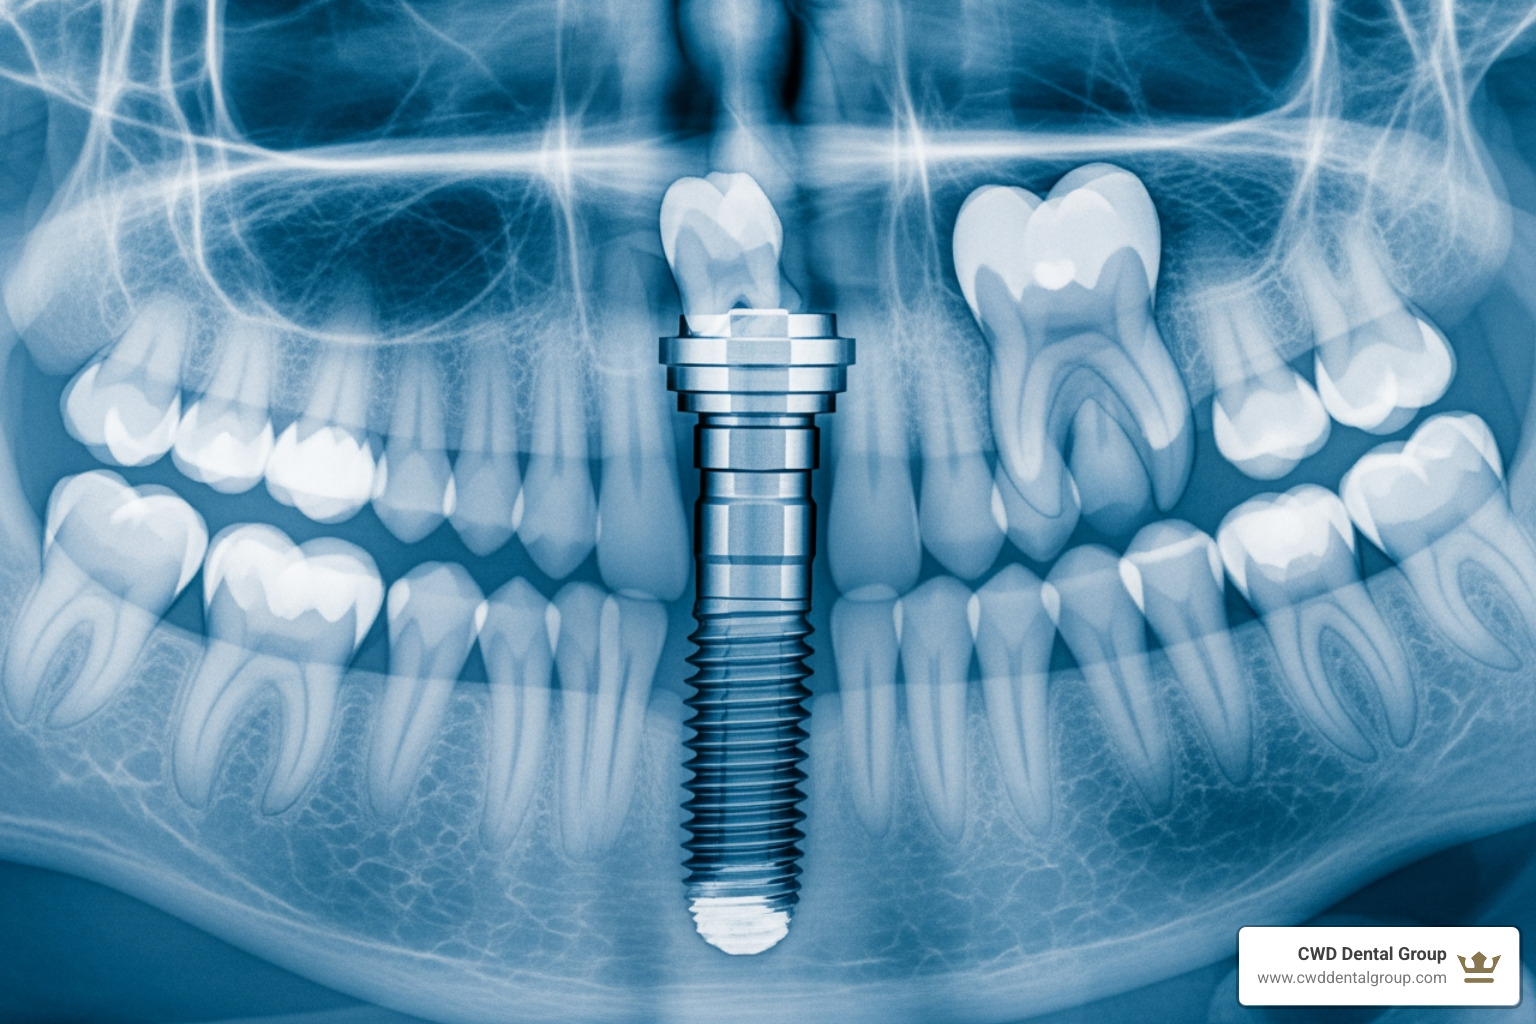

Dental implants are small titanium posts surgically placed into the jawbone. Through a process called osseointegration, they fuse with the bone to create a permanent foundation for replacement teeth. Unlike bridges or dentures, implants replace the entire tooth structure, preserving your jawbone and preventing the facial sagging that often accompanies tooth loss. The result is a replacement that looks, feels, and functions just like a natural tooth.

- The titanium implant post is the foundation. Surgically placed into your jawbone, it fuses with the bone through osseointegration. The surgical placement in Tallahassee typically costs around $1,740.

Before the procedure, an initial consultation and 3D imaging (like a CT scan) are necessary. This advanced technology allows us to map your jawbone and plan the precise placement of your implant, ensuring a smooth procedure and long-lasting results. The $3,500 to $5,500 range covers this complete package, from consultation to your final tooth.

Endosteal implants are the most common type, placed directly into the jawbone. The $3,500-$5,500 single-implant cost primarily refers to this gold-standard option. Subperiosteal implants, which sit on top of the bone, are a less common alternative for patients with significant bone loss.